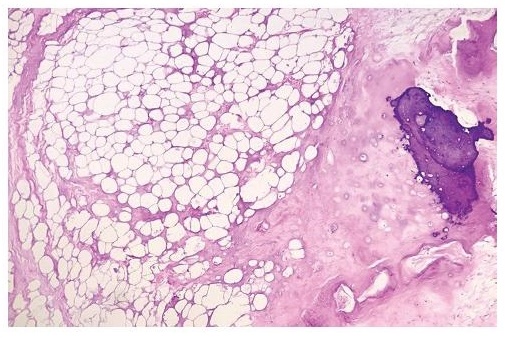

Gross examination showed yellow to cream/yellow, ovoid, fibrofatty to firm tissue with cream/white to cream/yellow smooth, glistening cut sections, with patchy areas of calcifications and fibrosis. Histopathologic examination showed mature adipose tissue with admixed mature lamellar bone (Figure 1) and areas with hyaline cartilage undergoing ossification (Figure 2). The adipocytes were monotonous and monomorphic. There was no nuclear atypia, lipoblasts, mitotic activity, or necrosis seen. The case was signed out as osteolipoma.

Figure 1. Mature adipose tissue with admixed mature lamellar bone (Hematoxylin & Eosin, 40x).